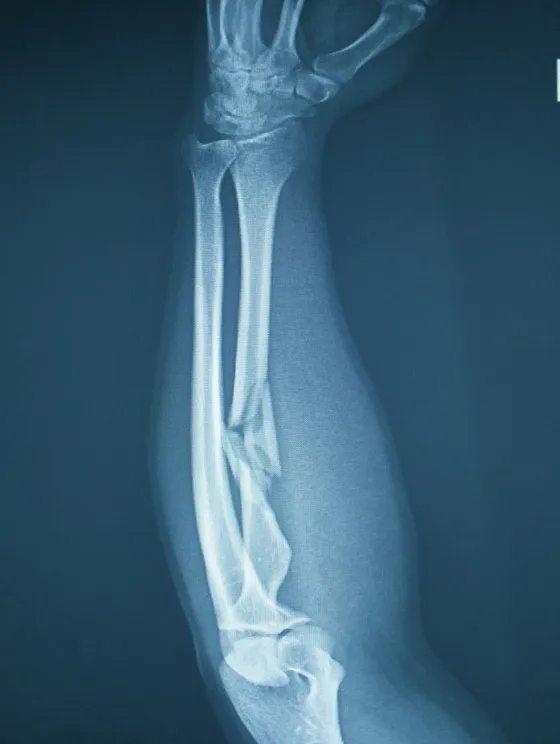

Post-Accidentes Fracturas con dolor crónico, lesiones de columna, trauma craneoencefálico con secuelas, daño de tejidos blandos que no regeneraron

Fracturas Complejas Pseudoartrosis (fracturas que no consolidan), edema óseo, consolidación retrasada, dolor post-fractura crónico